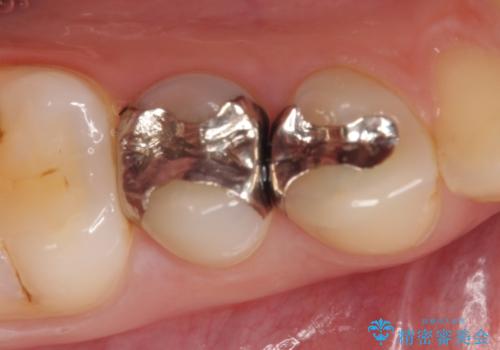

- 右下4、5番目の銀歯を白くしたいといらっしゃった方の症例です。

銀歯を除去後、セラミックインレーによる修復を行いました。